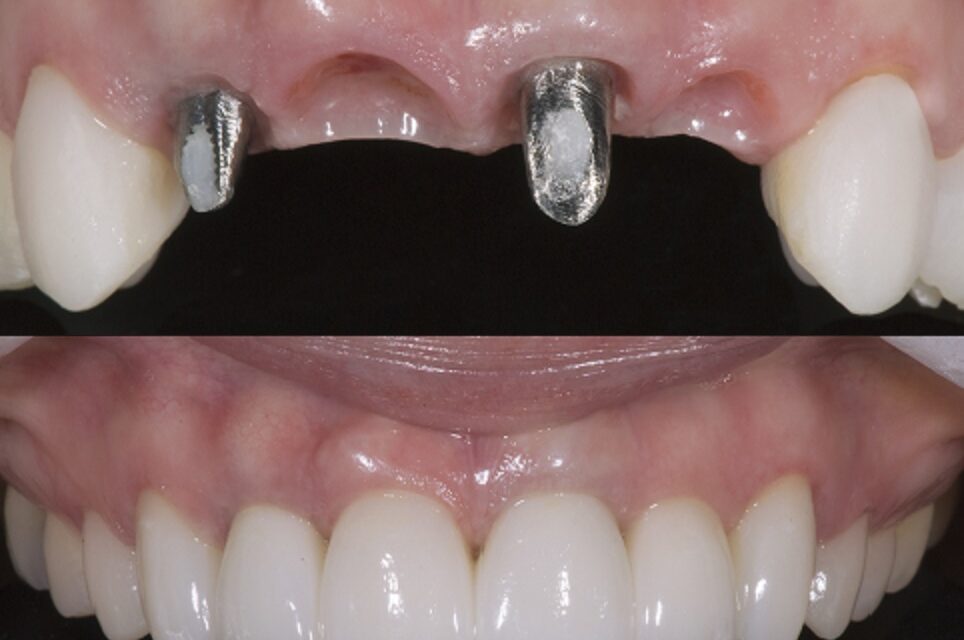

C. Full-Arch Fixed Prosthesis (Full-Arch Bridge / Hybrid Denture)

✪Entire jaw replaced with a fixed prosthesis on multiple implants (usually 4–8).

Common Designs:

All-on-4 / All-on-6 concept

Hybrid prosthesis (metal framework + acrylic/ceramic teeth)

Full zirconia or porcelain bridge

✅ Advantages:

Feels like natural teeth

Excellent stability and chewing efficiency

No need for removal